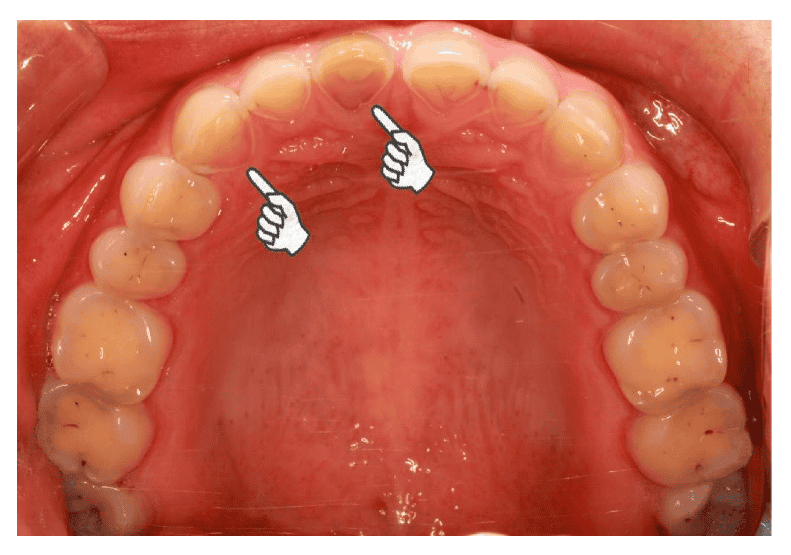

نشانه های رفلاکس اسید روی دندان ها

نشانه های رفلاکس اسید روی دندان ها اغلب تا زمانی که آسیب قابل توجهی رخ نداده باشد، قابل توجه نیستند. با گذشت زمان، این می تواند منجر به بروز سایر مشکلات دندانی مانند موارد زیر شود.

- افزایش حساسیت دندان، بویژه به غذاهای گرم، سرد یا شیرین.

- تغییر رنگ یا زرد شدن دندان ها با ساییدگی مینای دندان.

- لبه های ناهموار یا نازک شدن دندان ها، که باعث می شود کوچکتر به نظر برسند.

- دندان های زبر یا ناهموار.

- نمایان شدن عاج زیرین.

اسید چگونه به دندان ها آسیب می رساند؟

وقتی اسید معده به دهان شما راه پیدا می کند، پایین بودن مزمن pH دهان شروع به فرسایش مینای دندان، لایه بیرونی سخت و محافظ دندان های شما، می کند. این وضعیت به عنوان فرسایش دندان ناشی از رفلاکس اسید یا فرسایش اسیدی مینای دندان شناخته می شود که مینای دندان را تضعیف می کند و دندان های شما را در برابر پوسیدگی و حساسیت آسیب پذیرتر می کند. در موارد رفلاکس اسید، اغلب شاهد نازک شدن یا ساییدگی تدریجی مینای دندان های عقب هستیم. با ساییده شدن مینای دندان توسط اسید، ساختار زیرین دندان که رنگ زرد تیره تری دارد، شروع به نمایان شدن می کند. این امر منجر به ظاهر زرد کلی دندان ها می شود.